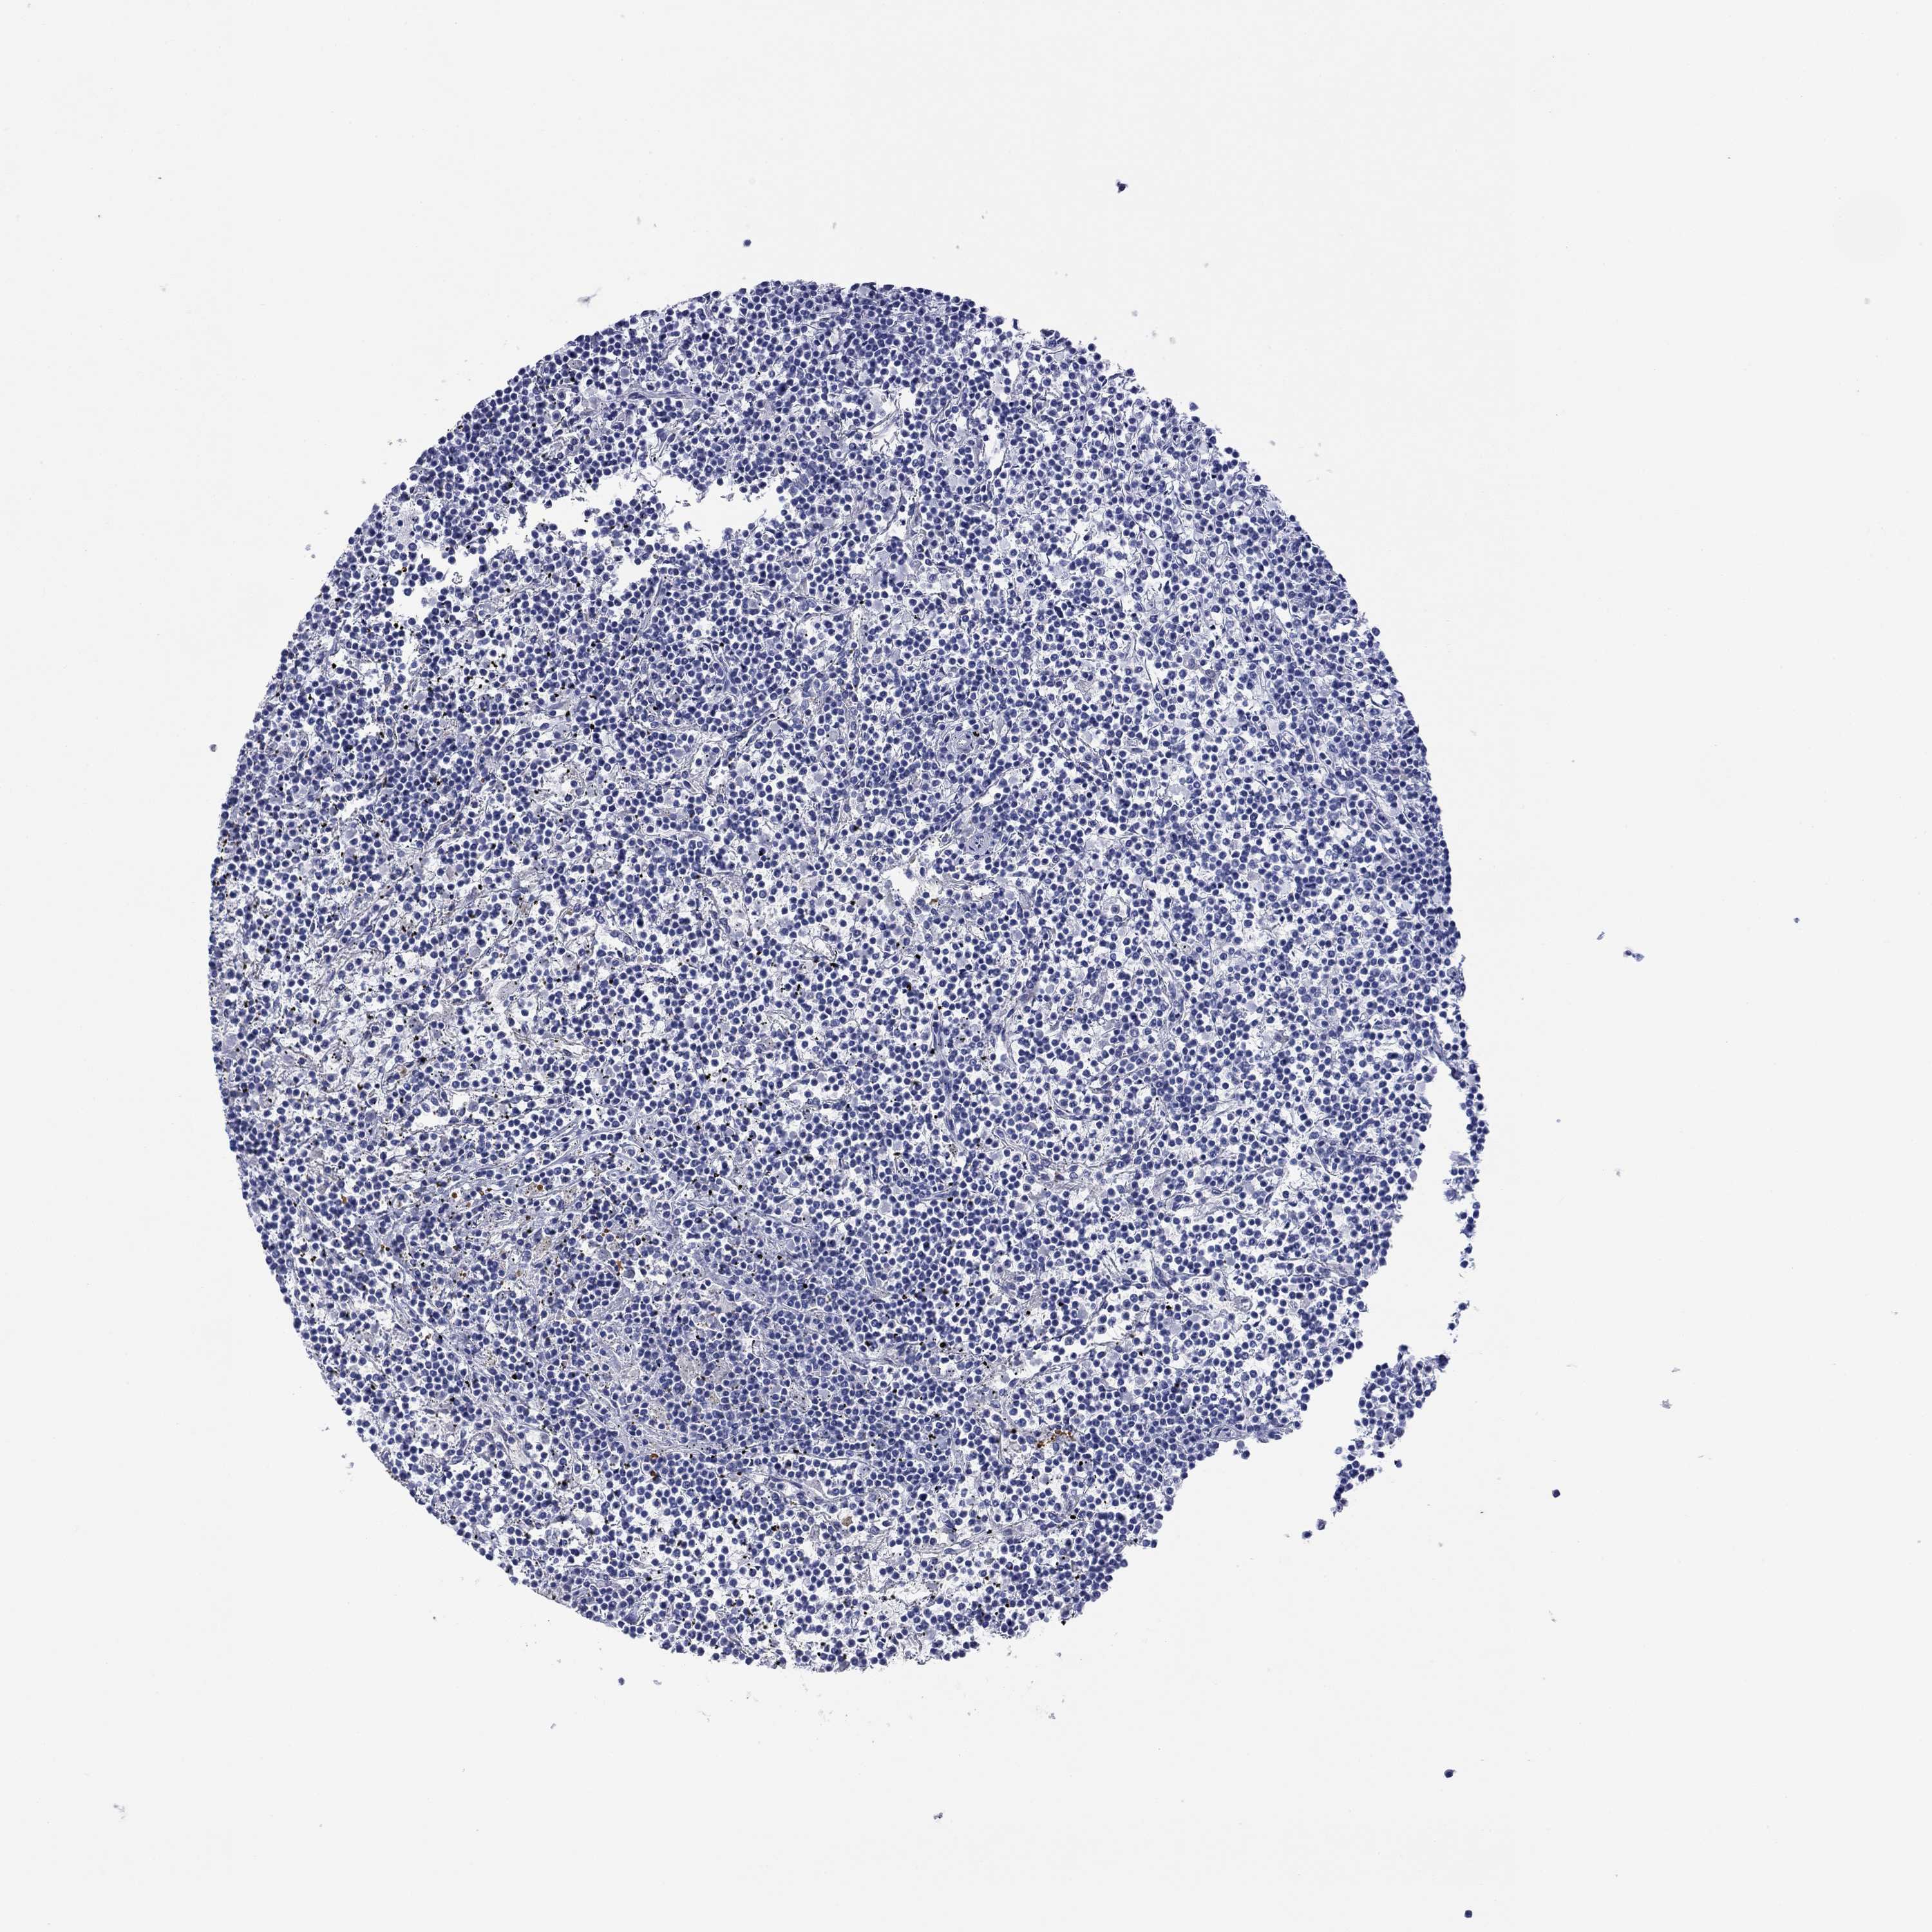

LYMPHOMA - Protein expressioni

A mouse-over function shows sample information and annotation data. Click on an image to view it in a full screen mode. Samples can be filtered based on level of antibody staining by selecting one or several of the following categories: high, medium, low and not detected. The assay and annotation is described here.

Antibody stainingi

Antibody staining in the annotated cell types in the current human tissue is reported as not detected, low, medium, or high, based on conventional immunohistochemistry profiling in selected tissues. This score is based on the combination of the staining intensity and fraction of stained cells.

Each image is clickable and will lead to virtual microscopy that enables deeper exploration of all samples and also displays staining intensity scores, fraction scores and subcellular localization as well as patient and tissue information for each sample.

Antibody HPA012911

Staining

High

Intensity

Strong

Quantity

>75%

Location

Cytoplasmic/membranous

Malignant lymphoma, non-Hodgkin's type, Low grade